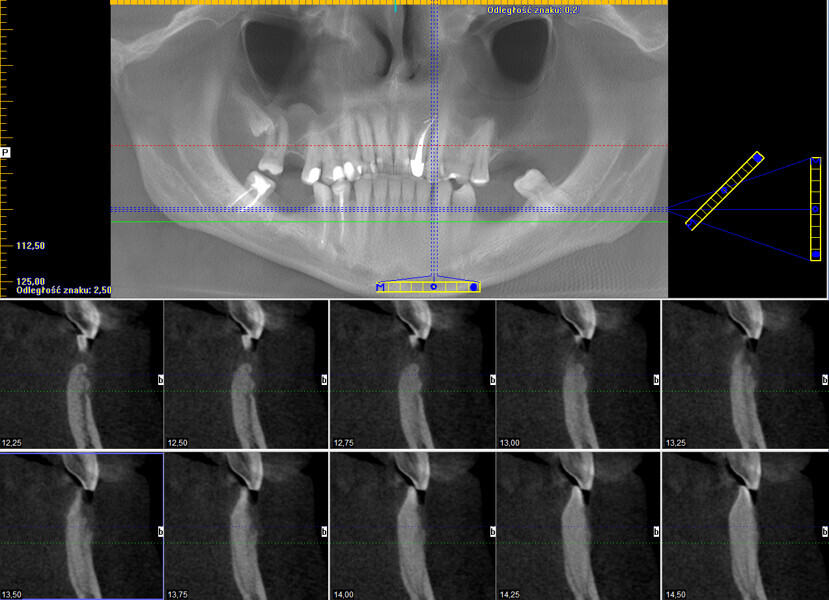

Śródkostna postać torbieli naskórkowej zlokalizowana w żuchwie – opis przypadku